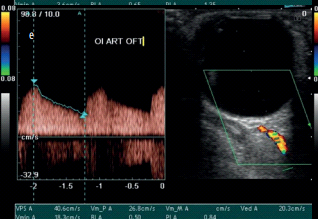

Once the optimal image of the explored vessel is obtained, with the necessary anatomical knowledge, the spectral record is visualized for the calculation of the desired parameters, placing the sample volume selectively in each of these vessels; for example: velocity at peak systolic (maximum) in cm/sec (VPS); velocity at end diastole (minimum) in cm/sec (VDF); resistance index (IR) or Pourcelot index corresponding to the equation (Figure 5).

Figure 5 Estimation of arterial velocimetric parameters.

We can visualize the intracerebral circulation by means of four ultrasound windows that identify a specific vascular group according to the acoustic characteristics of each vessel, which are summarized in (Table 1).

Parameter

AO

ACR

Lateral ACP

Medial ACP

VSM (cm/sec)

45,3 ± 10,5

(31,4-39,6 )

17,3 ± 2,6

(8,8-12,6)

13,3 ± 3,5

(9,8-11,4)

12,4 ± 3,4

(8,6-14,2)

VDP (cm/sec)

11,8 ± 4,3

(8,2-10,6)

6,2 ± 2,7

(2,0-4,0)

6,4 ± 1,5

(3,4-1,7)

5,8 ± 2,5

(3,3-4,9)

IR

0,74 ± 0,07

(0,73-0,81)

0,63 ± 0,09

(0,70-0,76)

0,52 ± 0,10

(0,63-0,68)

0,53 ± 0,08

Table 1 Reference sonographic parameters of retrobulbar arterial vascular structures (Argentine Society of Cardiology)20